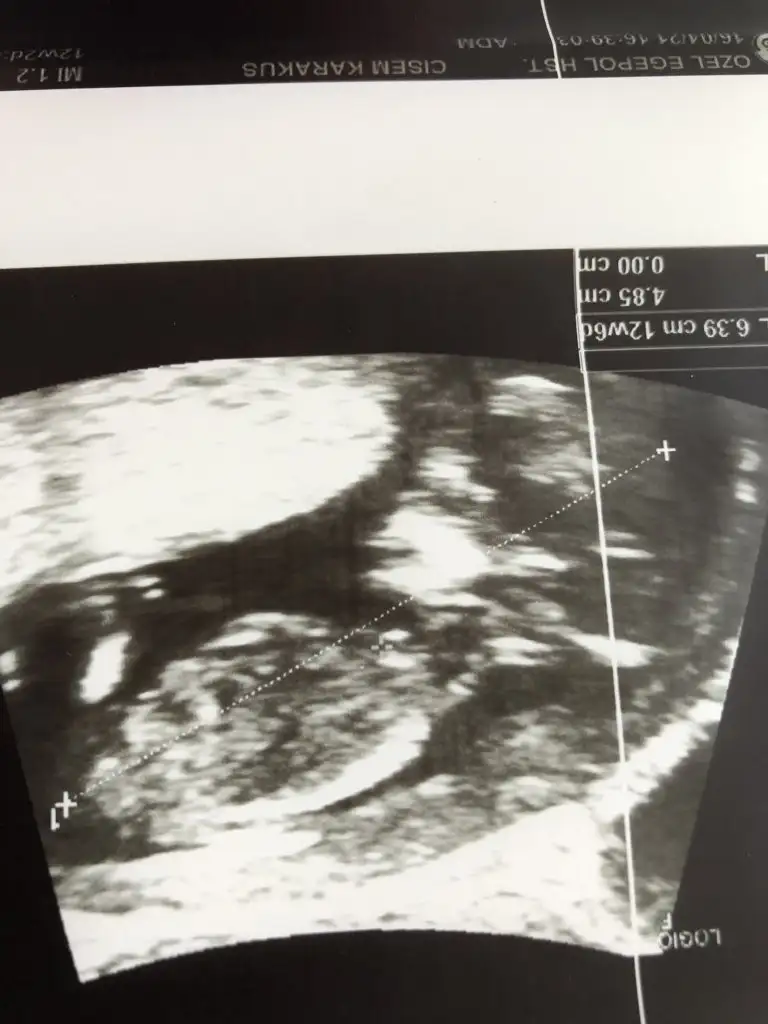

[/B]Eki Görüntüle 473828 gordugunuz gibi ust taraftaki simgedende anlasildigi gibi eger cikinti paralel ise kiz

yok 30°lik bir aciyla yukari dogru bakiyorsa %99 oglunuz olacak demektir simdi bi kac ornek resimler daha koyacagim kiziminkide dahil

Eki Görüntüle 473831 simdi burada cikintilara bakin eger bel popo cizgisine paralel ise kiz

yok 30 derecelik bir aciyla yukari bakiyorsa erkek

iste o nub teorisi kizlar dr buradan yola cikiyor